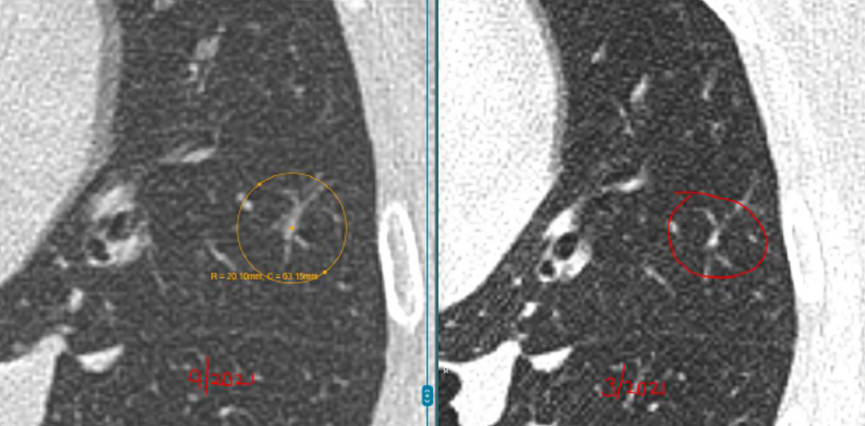

具体来看,右肺有一个磨玻璃结节(约4mm),左肺还有两个实性结节(约5mm、3mm)。

之后的4年里,这3枚小结节都没有什么变化,这让她逐渐放下心来。

然而在随后的一次复查中,CT结果显示磨玻璃结节“密度略微增加”,而且又新出现了一枚3mm的小结节。

“先看左肺这两枚实性结节,它们在这几年一直很稳定,没有明显增大,形态也没有变化。像这类稳定超过3年的小实性结节,良性可能性超过了99%。从片子上看,它们更像是肺部之前因为旧损伤留下的痕迹。”L教授说。

关于右肺的4mm磨玻璃结节,L教授对比了新旧影像,并不认为它在恶化。

“这一枚,是您现在担心的,对吗?因为报告里提到它的密度比以前稍微高了一点。但从影像上看,这种变化还是非常轻微的,目前还没有达到让我们怀疑它正在明显恶化的程度。它确实值得继续随访,但至少以现在这个状态,还谈不上需要立刻处理,更不意味着已经朝着癌的方向快速发展。”L教授说。

关于右肺新出现的那枚大约3mm的磨玻璃结节,L教授同样为林女士进行了详细解释。

他指出,很多人一听到出现新发结节,马上会非常紧张,觉得可能是冒出了不好的东西。其实不是这样。

“像这么小、这么淡的磨玻璃结节,在临床上很常见,很多时候更像是一过性的炎性反应,可能和轻微感染甚至短期肺部状态变化有关。有些结节过一段时间复查,自己就消失了。所以对这枚结节,我目前更倾向于把它看作一个温和的、需要观察的信号,而不是一个必须马上干预的问题。”L教授说。

L教授总结道:“总体来看,您现在这4枚结节都还很小,而且没有哪一枚表现出必须马上手术或活检的证据。左肺两枚实性结节长期稳定,右肺原有的磨玻璃结节虽然密度略有变化,但幅度很小,新发的3mm磨玻璃结节也更像炎性改变。换句话说,它们都还没有到‘该切的时候’。现阶段继续按计划随访,是安全的,也是更合理的做法。”